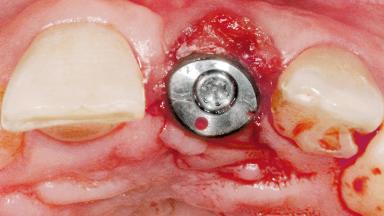

Early Placement of an Implant in a Maxillary Right Central Incisor Site

This 41-year-old female patient was referred to the clinic for the replacement of the right central incisor, since the tooth had developed a root fracture in the long axis that made extraction necessary. The healthy, non-smoking patient was first seen with the tooth still in place. A detailed Esthetic Risk Assessment was performed.The patient was worried about her dental esthetics and had high expectations for a successful treatment outcome from an esthetic point of view. The patient had a medium lip line that displayed parts of the gingiva in the anterior maxilla upon smile.

Defining Characteristics One missing tooth to be replaced by an implant-borne prosthesis

Bone Volume Deficient horizontally, allowing simultaneous augumentation

Esthetic Risk High